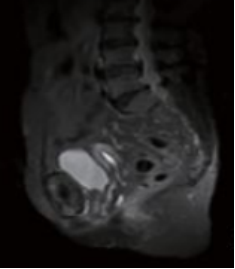

3.磁共振扫描(MRI)

影像学表现为:耻骨联合间隙可不同程度增宽,间隙内可见带状透亮间隙,单侧或双侧耻骨联合骨缘局限骨质硬化,少数囊变;耻骨联合骨缘锯齿状、鼠咬状、虫蚀状骨质破坏,边缘不光整,有时可见游离小骨块,早期骨质呈长T1长T2信号,晚期骨质均呈低信号。